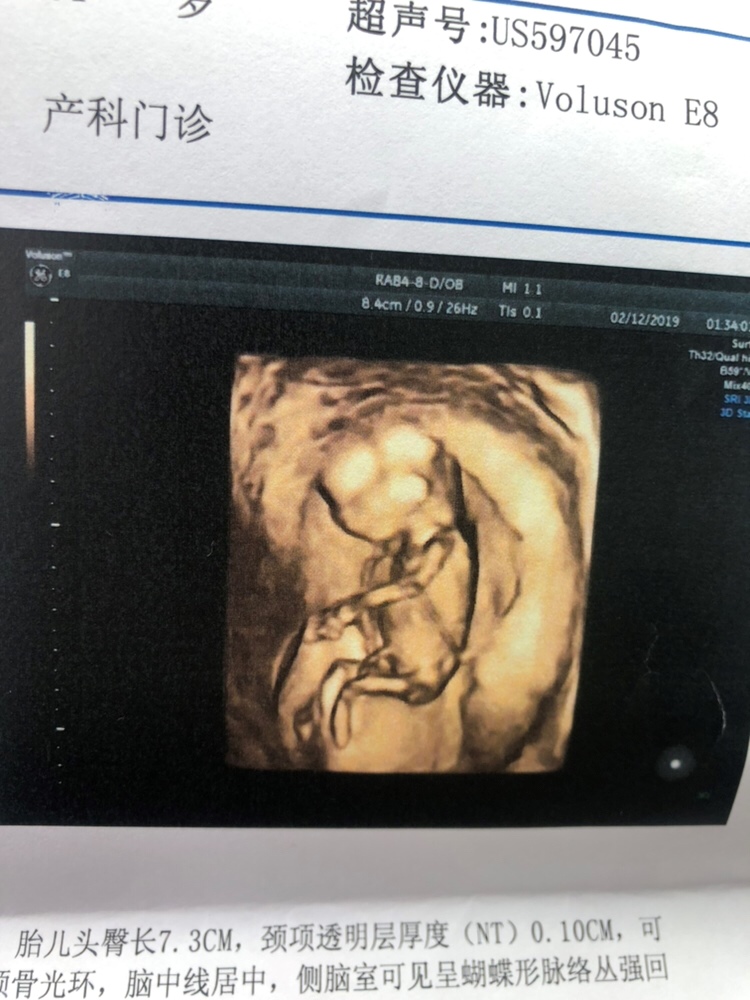

孕13周+5天

恭喜恭喜,接Nt顺利通过

我也是永康,怀孕时间也差不多,我也刚做了NT